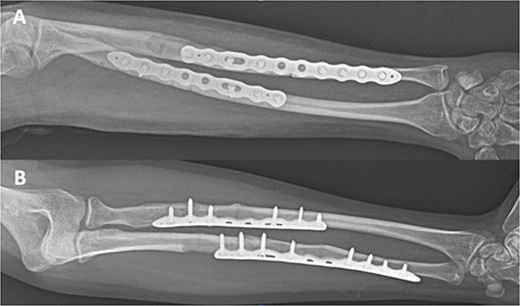

A 32-year-old male was referred to the emergency room after a sport accident. Fourteen months previously, he successfully underwent osteosynthesis with two 3.2 mm stainless steel locking plate (Trimed Elbow Forearm System™, CA, USA) for a radial (six-holes) and ulnar (seven-holes) shaft fractures after a sport accident. On admission, X-rays revealed a NPPIF of both forearm bones (Fig. 1), classified as P1A type [2]. The fracture was just distal to the edge of the last screw of both plates. The patient underwent both hardware removal, reduction of the fractures and fixation using two 3.5 mm longer titanium dynamic compression plate for the radial (eight holes) and ulnar (10 holes) shaft fracture (Stryker Corporation Kalmazoo, MI, USA). After that, the patient was referred for physical therapy and rehabilitation. A total of 3 months after surgery, complete bone healing was observed (Fig. 2). At final follow-up, 36-months after surgery, the patient’s elbow extension and flexion was from 0° to 130°, wrist pronation and supination was from 90° to 75°, and wrist flexion and extension were 75° and 70° were completely painless. His grip strength was 93% that of the opposite hand.

Internal fixation of both NPPIFs with a longer plate that bridges the original fracture zone and the new NPPIF. Final follow-up at 36 months after surgery, anterior–posterior X-ray.